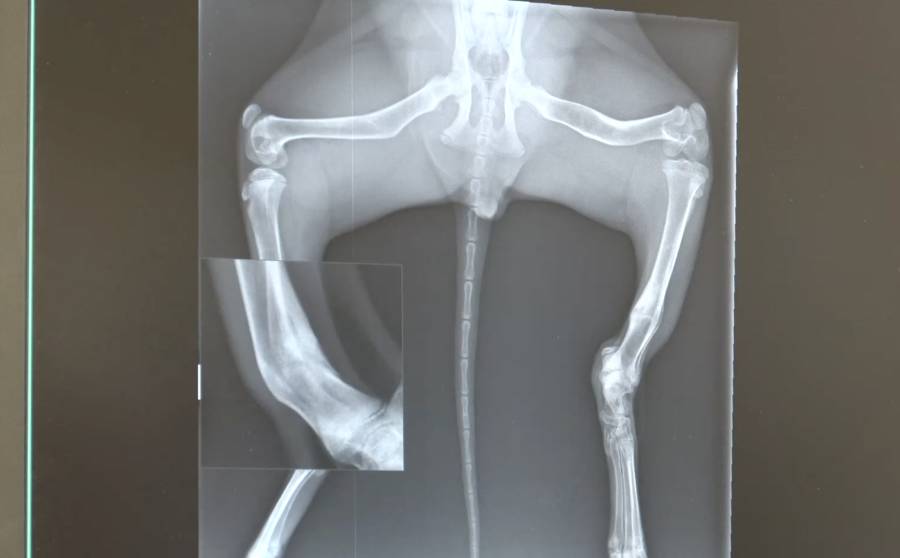

Radiografía de uno de los servales rescatados por AAP que presenta fracturas debido a los deficientes cuidados